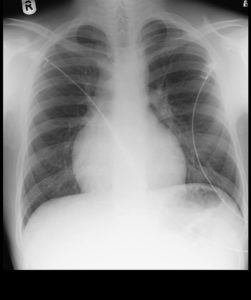

Normal Heart Size & Lt.Ventricle

Heart Enlarged